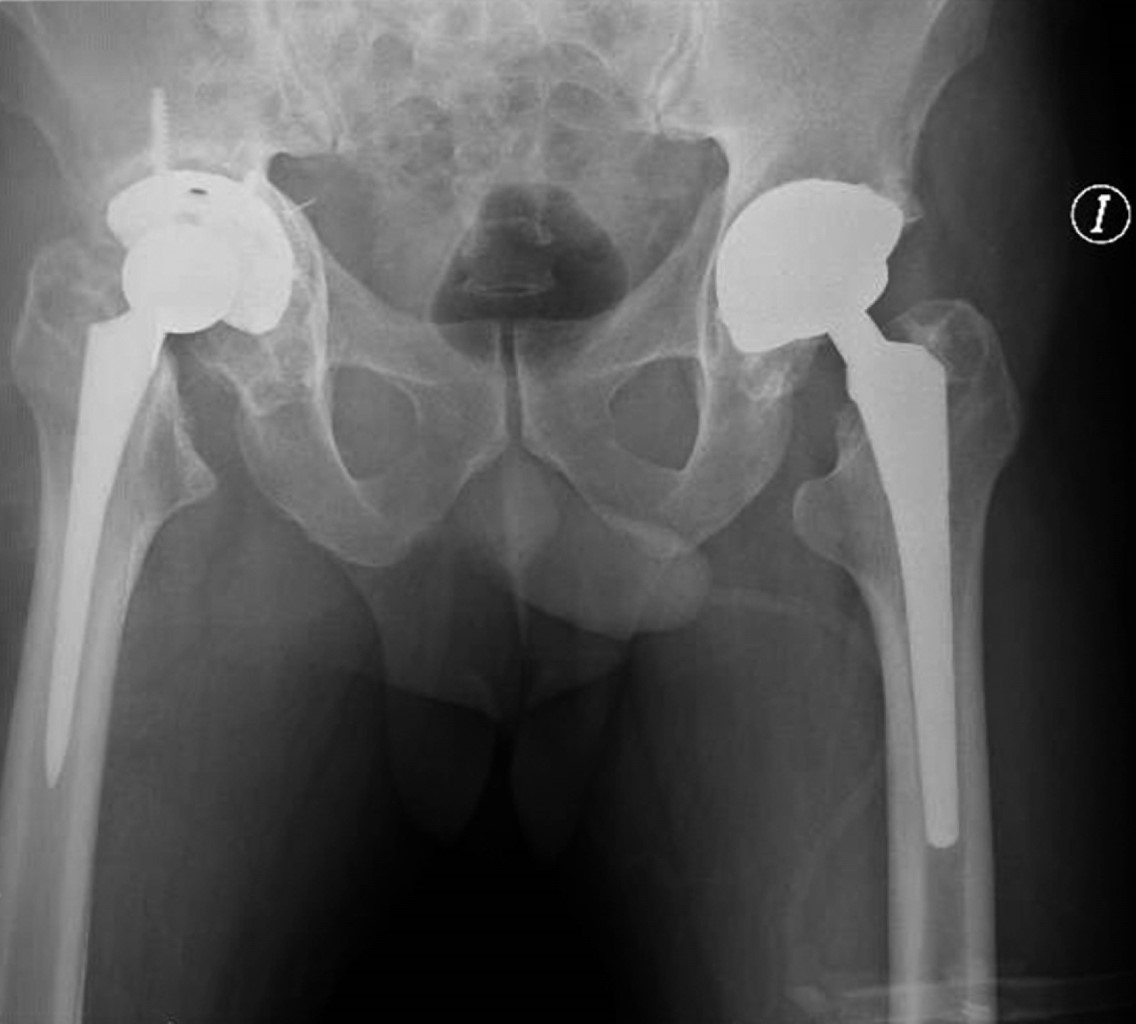

La artroplastía total de cadera se realizó con una prótesis con sistema DePuy Synthes de Johnson & Johnson (Warsaw, IN, USA) con una copa acetabular no cementada Pinnacle Porocoat Acetabular Shell Multi-Hole II de 58 mm, la cual se fija con tres tornillos de 6.5 × 20,2 y 30 mm,1 inserto de polietileno de 32 mm, cabeza femoral metálica de 32 mm +1 y vástago femoral no cementado Summit 12/14 estándar #1 de 125 mm. El reemplazo articular se llevó a cabo por medio de un abordaje lateral directo donde, previo a la colocación del componente acetabular, se impacta autoinjerto y aloinjerto de cabeza femoral con el apoyo de la rima acetabular en sentido reverso para posteriormente colocar malla de titanio (Figura 5). La herida se cubre con un apósito convencional estéril y se toma control radiológico postquirúrgico con una proyección anteroposterior de pelvis (Figura 6).

Figura 2

Figura 5

Figura 6